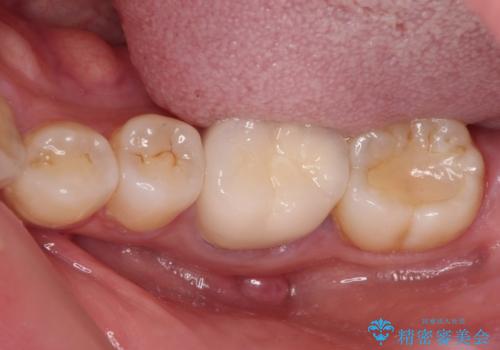

- 上下の奥歯に違和感を感じ、近医にて虫歯を指摘されたとのことで来院された患者様です。

診査したところ、下顎の奥歯は膿の出口ができており、上顎の奥歯は噛んだときに痛みを感じている状態でした。

まずは根管治療を行い、症状が落ち着いたことを確認して、オールセラミッククラウンにて補綴治療を行うこととしました。